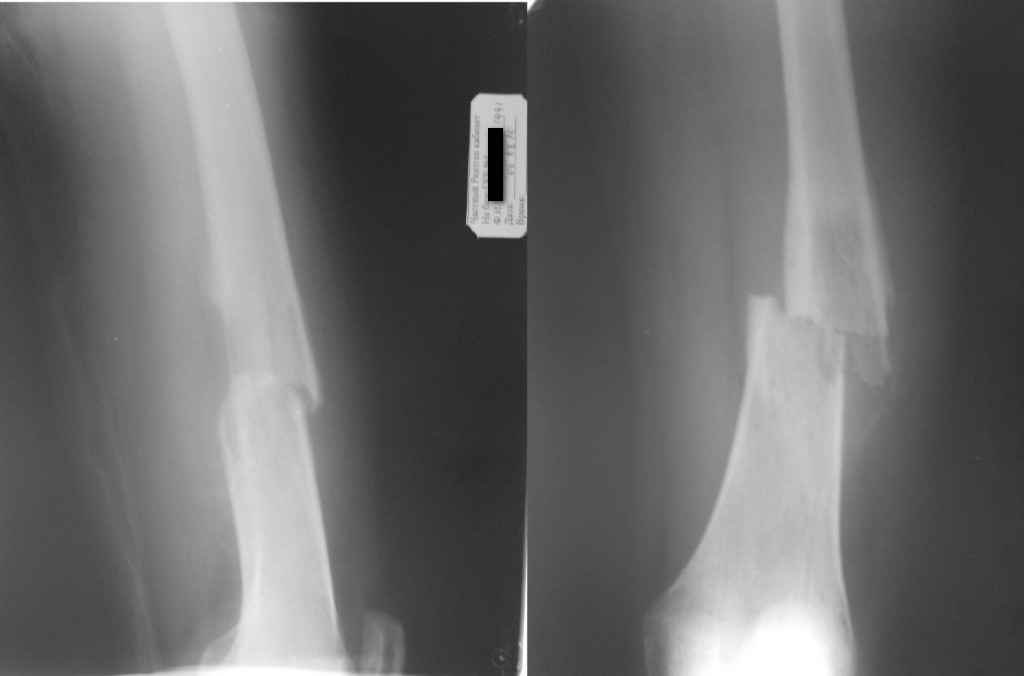

больной 18 лет, студентка I курса медуниверситета. Травма исключается, во время ходьбы почувствовала боли в области с/3 правого бедра и упала. Со слов в течени последних 2 месяца появилось опухоль в области с/3 правого бедра.

Имеется мягкотканный компонент на бедре. Снимки во вложении.Наш предварительный диагноз после консультации онколога: Саркома бедренной кости с двухсторонним поражением легкого.(Рентгенолог указывает на МТС легких).